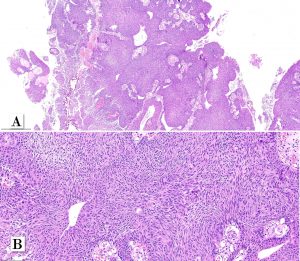

A male patient in his early 70s underwent surgical removal a single pedunculated 3 cm polypoid tumor in the bladder mucosa at the left lateral wall.

Papillary urothelial carcinoma, noninvasive, whorled subtype

One rare morphologic subtype of in noninvasive papillary urothelial carcinoma has been described as a whorled pattern. Patriarca et al. 2014 described a series of 12 patients: all noninvasive and most of them 11/12 classified as low-grade. One patient had a tumor with mixed grade (5% of the tumor at other areas. Whorled pattern shows concentrically organized cell structures, without morphological evidence of keratinization, similar to the whorling structures of transitional meningioma.

In that series, none of the cases experienced T1 stage progression and two recurrences occurred. One of the recurrent tumors was the one harboring small focus of high-grade tumor inside the primary lesion. Interestingly, the recurrent cases maintained the same whorling pattern in the second transurethral resection specimens. Therefore, although limited data on follow up is available, clinical behavior seems to be similar to low-grade noninvasive papillary urothelial carcinoma (Patriarca et al. 2014). Awareness of this morphologic subtype is important to avoid misclassification of other epithelial lesions which may show squamous or squamoid morphology.